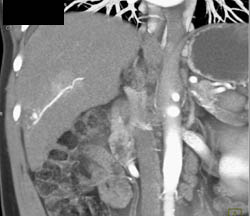

Hemangioma